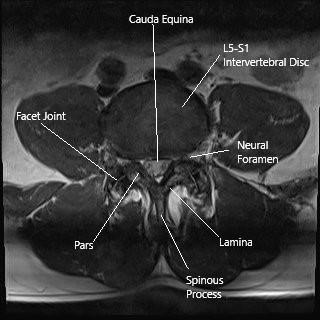

One of the trickiest parts in lower limb claudication is making sense of the overlapping symptoms that share a common root. In a recent report concerning a 60-year-old male with a background of coronary artery disease, the symptoms ranged from persistent lumbosacral back pain to progressive bilateral leg claudication. The patient’s history, marked by significant cardiovascular risk factors including smoking and dyslipidemia, suggested vascular issues at first glance. However, careful imaging revealed a lumbar facet joint synovial cyst that was compressing the spinal canal.

Modern imaging techniques have revolutionized the ability to pinpoint both obvious and hidden issues. For patients with suspected lower limb claudication, MRI stands as the gold standard for exploring spinal degeneration, including conditions such as lumbar facet joint synovial cysts. These cysts form due to degeneration of the facet joint and may impinge on the spinal canal, triggering neurogenic pain.